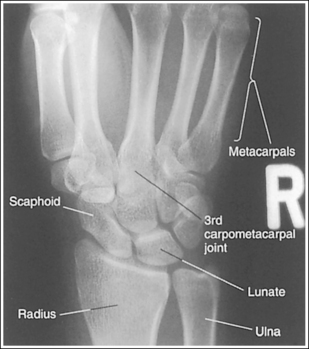

See Figure 4-29 and Box 4-11.

Contrast and density are adequate to demonstrate the scaphoid fat stripe.

• Significance of the scaphoid fat stripe. The scaphoid fat stripe is one of the soft tissue structures that should be visible on all PA wrist projections (Figure 4-30). It is convex and located just lateral to the scaphoid in an uninjured wrist. A change in the convexity of this stripe may indicate to the reviewer the presence of joint effusion or of a radial side fracture of the scaphoid, radial styloid process, or proximal first metacarpal.

The wrist is positioned in a PA projection. The radial and ulnar styloids are at the extreme lateral and medial edges, respectively, of each bone. The radioulnar articulation is open, and superimposition of the metacarpal bases is limited.

• Rotation of the wrist and forearm is controlled by the position of the hand, elbow, and humerus. A PA projection is accomplished by abducting the humerus until it is positioned parallel with the IR and the elbow is in a lateral projection. The hand is then pronated, placing the wrist in a PA projection (Figure 4-31).

The second through fifth CM joint spaces are open. The scaphoid is only slightly foreshortened, and the lunate is trapezoidal.

The long axes of the third metacarpal and the midforearm are aligned with the long axis of the collimated light field. The scaphoid and half of the lunate are positioned distal to the radius.

• If the long axes of the third metacarpal and the midforearm are aligned with the long axis of the collimated light field, the patient's wrist has been placed in a neutral position. If a neutral position is not maintained for a PA wrist projection, the shapes of the scaphoid and the position of the lunate are altered (Figure 4-33; see Images 36 and 37). Radial deviation of the wrist causes the distal scaphoid to shift anteriorly (toward the palmar surface) and to demonstrate increased foreshortening as it forms a signet ring configuration. The lunate will shift medially, toward the ulna. In ulnar deviation, the distal scaphoid tilts posteriorly and demonstrates decreased foreshortening, and the lunate shifts laterally, toward the radius. Radial and ulnar deviated PA wrist projections may be specifically requested to demonstrate wrist joint mobility.

Figure 4-33 PA wrist in radial deviation (left) and ulnar deviation (right). (From Martensen K II: Radiographic positioning and analysis of the wrist, In-Service Reviews in Radiologic Technology, 16[5], 1992.)

The carpal bones are at the center of the exposure field. The carpal bones, one fourth of the distal ulna and radius, and half of the proximal metacarpals are included within the collimated field.

• The wrist joint is located at a level just distal to the palpable ulnar styloid. To obtain an image of the carpal bones with the least amount of distortion, place a perpendicular central ray at this level and centered to the midwrist area. Open the longitudinal collimation to include half of the metacarpals. Transversely collimate to within 0.5 inch (1.25 cm) of the wrist skin line.

See Figure 4-34 and Box 4-12.

• The scaphoid fat stripe is one of the soft tissue structures that should be visible on all PA oblique wrist projections. It is convex and located just lateral to the scaphoid on an uninjured wrist (see Figure 4-30). A change in the shape of this fat stripe or in its proximity to the scaphoid may indicate joint effusion or a radial side fracture.

The wrist has been externally rotated to a 45-degree PA oblique projection. The trapezoid and trapezium are demonstrated without superimposition, and the trapeziotrapezoidal joint space is open. The scaphoid tuberosity and waist are demonstrated in profile. Only a small degree of trapezoid and capitate superimposition is present.

• To accomplish a PA oblique wrist projection, begin with the wrist in a PA projection, with the humerus and the forearm on the same horizontal plane. Externally rotate the hand and wrist until the wrist forms a 45-degree angle with the IR (Figure 4-35). When judging the degree of wrist obliquity, it is best to view the wrist and not the hand. The obliquity of the hand and wrist are not always equal when they are rotated, especially if the humerus and forearm are not positioned on the same horizontal plane for the image.